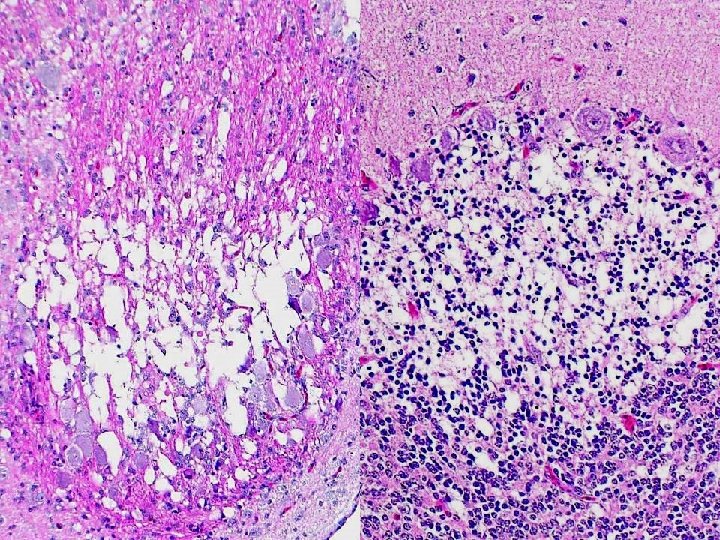

Myocardial degeneration, hearts - Ducks (Selenium/vitamin E deficiency)